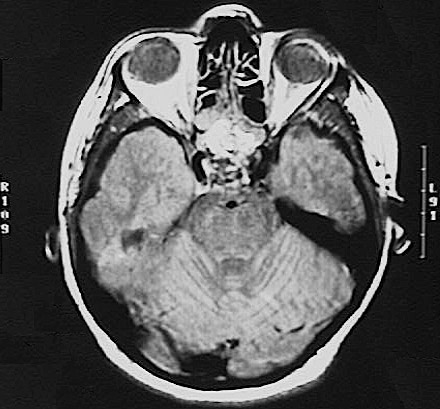

Click on the craniopharyngioma in the CT scan above:

This T1 weighted MRI scan in axial view demonstrates a mass with irregular margins in the region of the sella. Such a mass may impinge upon the optic chiasm, just like a pituitary adenoma. Craniopharyngiomas are uncommon and tend to occur in young persons.